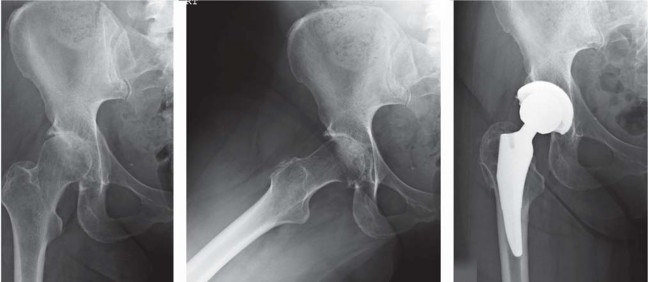

تُعد الأشعة السينية هي الأداة التشخيصية الأكثر أهمية. تُظهر الأشعة السينية مدى تآكل الغضروف، وتلف العظام، ووجود النتوءات العظمية (العظمية)، والتغيرات في بنية المفصل. يمكن أن تساعد هذه الصور في تأكيد تشخيص التهاب المفاصل أو غيره من الحالات التي تؤثر على الورك.

تحضير الفخذ والحق

يتم تحديد مستوى قطع عنق الفخذ مسبقًا بالتخطيط (باستخدام الأشعة السينية) ومواءمته أثناء الجراحة مع المدور الكبير. بعد قطع عنق الفخذ، يتم تحضير الحُق بالطريقة القياسية قبل تحضير الفخذ. يفضل الأستاذ الدكتور محمد هطيف عادةً وضع الكأس وفقًا للمعالم التشريحية لإعادة إنشاء التوجيه الطبيعي للحُق لدى المريض ويتحقق من الإصدار والميل الصحيحين عن طريق الجس والرؤية المباش